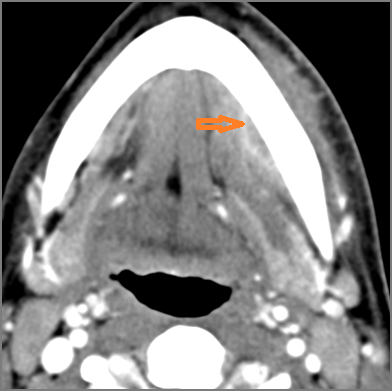

Vascular Findings

There is evidence of thrombus, thrombophlebitis or other occlusive or inflammatory process of the jugular vein or smaller venous tributaries. [Yes/No]

There is evidence of thrombus, inflammation of the common, external or internal carotid artery. [Yes/No]

There is evidence of active extravasation or a contained leakage from an arterial source. [Yes/No]